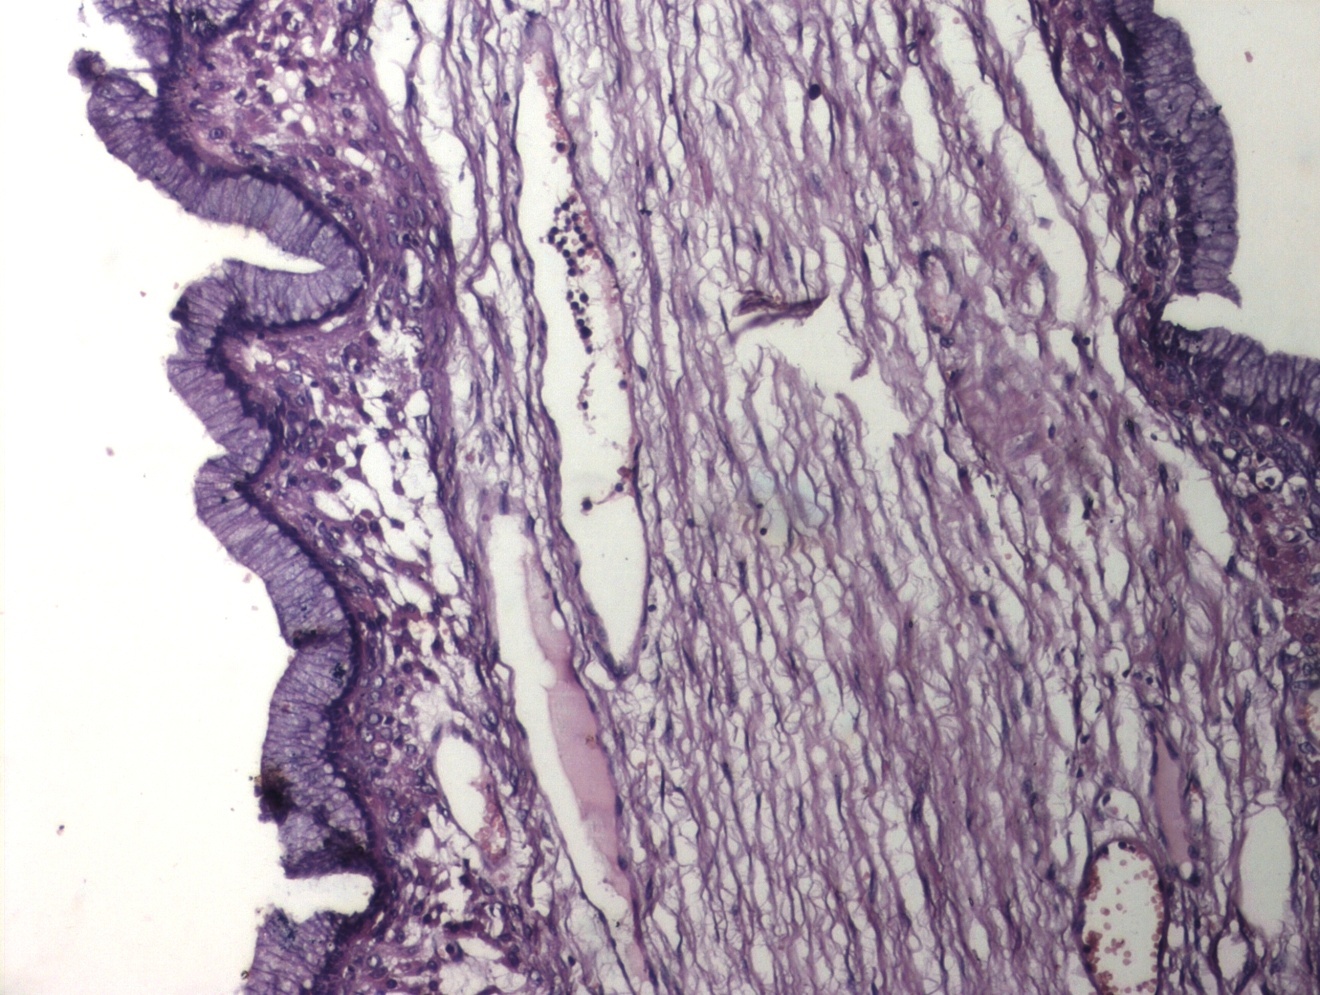

Mucinous cystadenoma of the ovary; a benign neoplasm accounts for 15% of all ovarian neoplasms. Being most prevalent in third to fifth decade, its incidence in adolescents is a rarity. These neoplasms vary in size from few centimeters to several centimeters and can weigh as heavy as a few kilograms. Grossly, mucinous neoplasms are characterised by cysts of variable sizes without surface invasion. Histologically, mucinous cystadenoma is lined by tall columnar non-ciliated epithelial cells with apical mucin and basal nuclei. They are classified according to the mucin-producing epithelial cells into three types. Mucinous neoplasms are classified into three types according to mucin producing epithelial cells namely endocervical, intestinal and mullerian [5]. Mucinous tumours are usually cystic, with 76% being multilocular and 24% unilocular. Only approximately 10% of mucinous tumours are bilateral, excluding metastatic spread to the contralateral ovary [5,6].

| Figure 2: Mucinous Cystadenoma Ovary (H&E, 100x) |